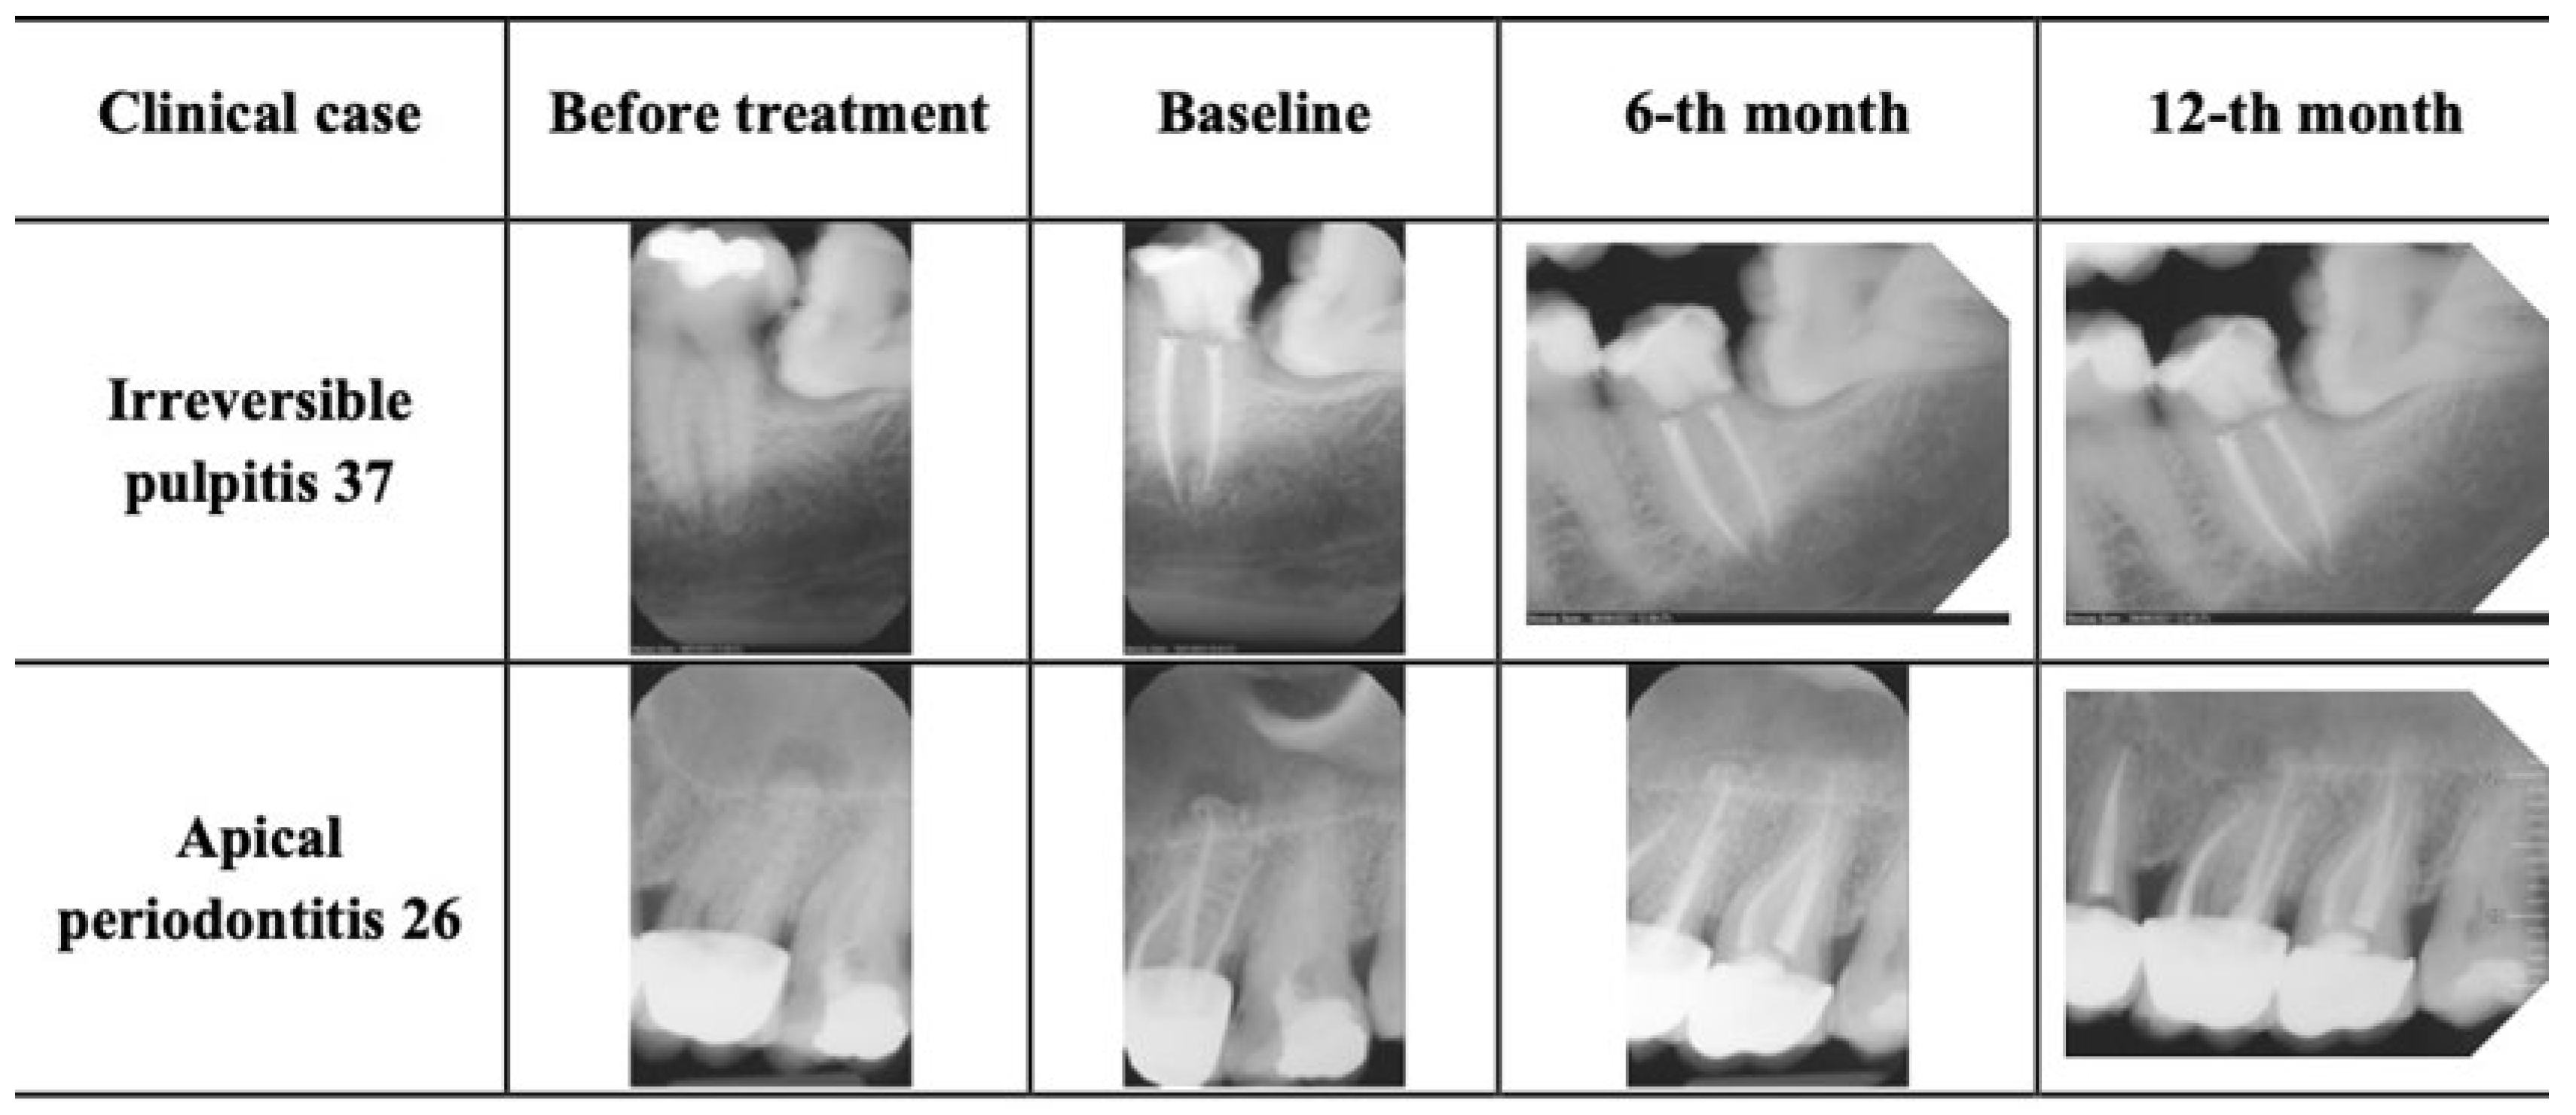

All patients were monitored postoperatively through recall visits and follow-up contact. No flare-ups requiring additional treatment were recorded. Transient postoperative discomfort occurred in approximately 3% of cases, typically resolving within 2–3 days without intervention. At both the 6- and 12-month recalls, all treated teeth were functional and symptom-free. Coronal restorations remained adequate, with no signs of fractures or secondary caries (Figure 2).

Figure 2. Representative radiographs of clinical cases.